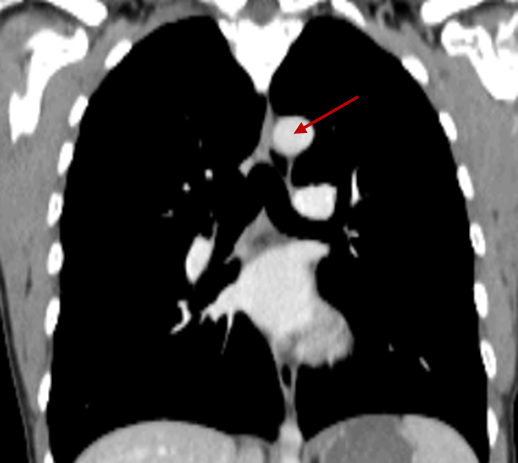

2.147 Zu sehen ist ein CT-Thorax. Welche der folgenden Strukturen wird hier mit dem roten Pfeil dargestellt?

Antwortmöglichkeiten

- (A) Trachea

- (B) Lymphknoten des Mediastinums

- (C) Angeschnitten der linke Lappen des Thymus

- (D) Aorta

- (E) V. Subclavia